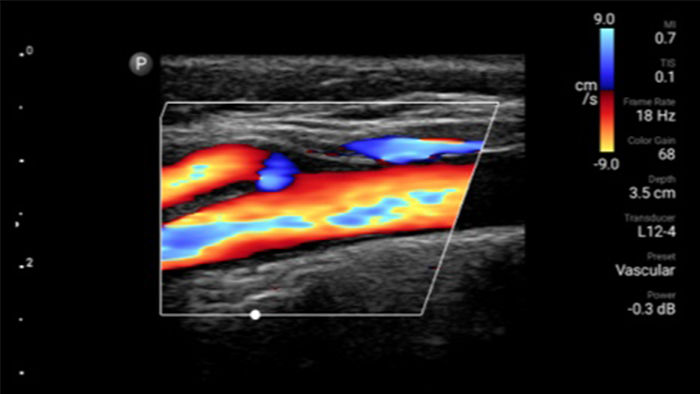

System Lumify pomaga wyraźnie zwizualizować wprowadzaną igłę, otaczające ją nerwy, naczynia oraz powierzchnie powięzi.

Od ukazania subtelnych detali obrazu do znakomitego odwzorowania tkanek pod różnymi kątami — system Lumify może pomóc w pewniejszym podejmowaniu decyzji klinicznych tu i teraz zarówno w przypadku wstępnej diagnostyki pacjenta, jak i podczas jego leczenia.